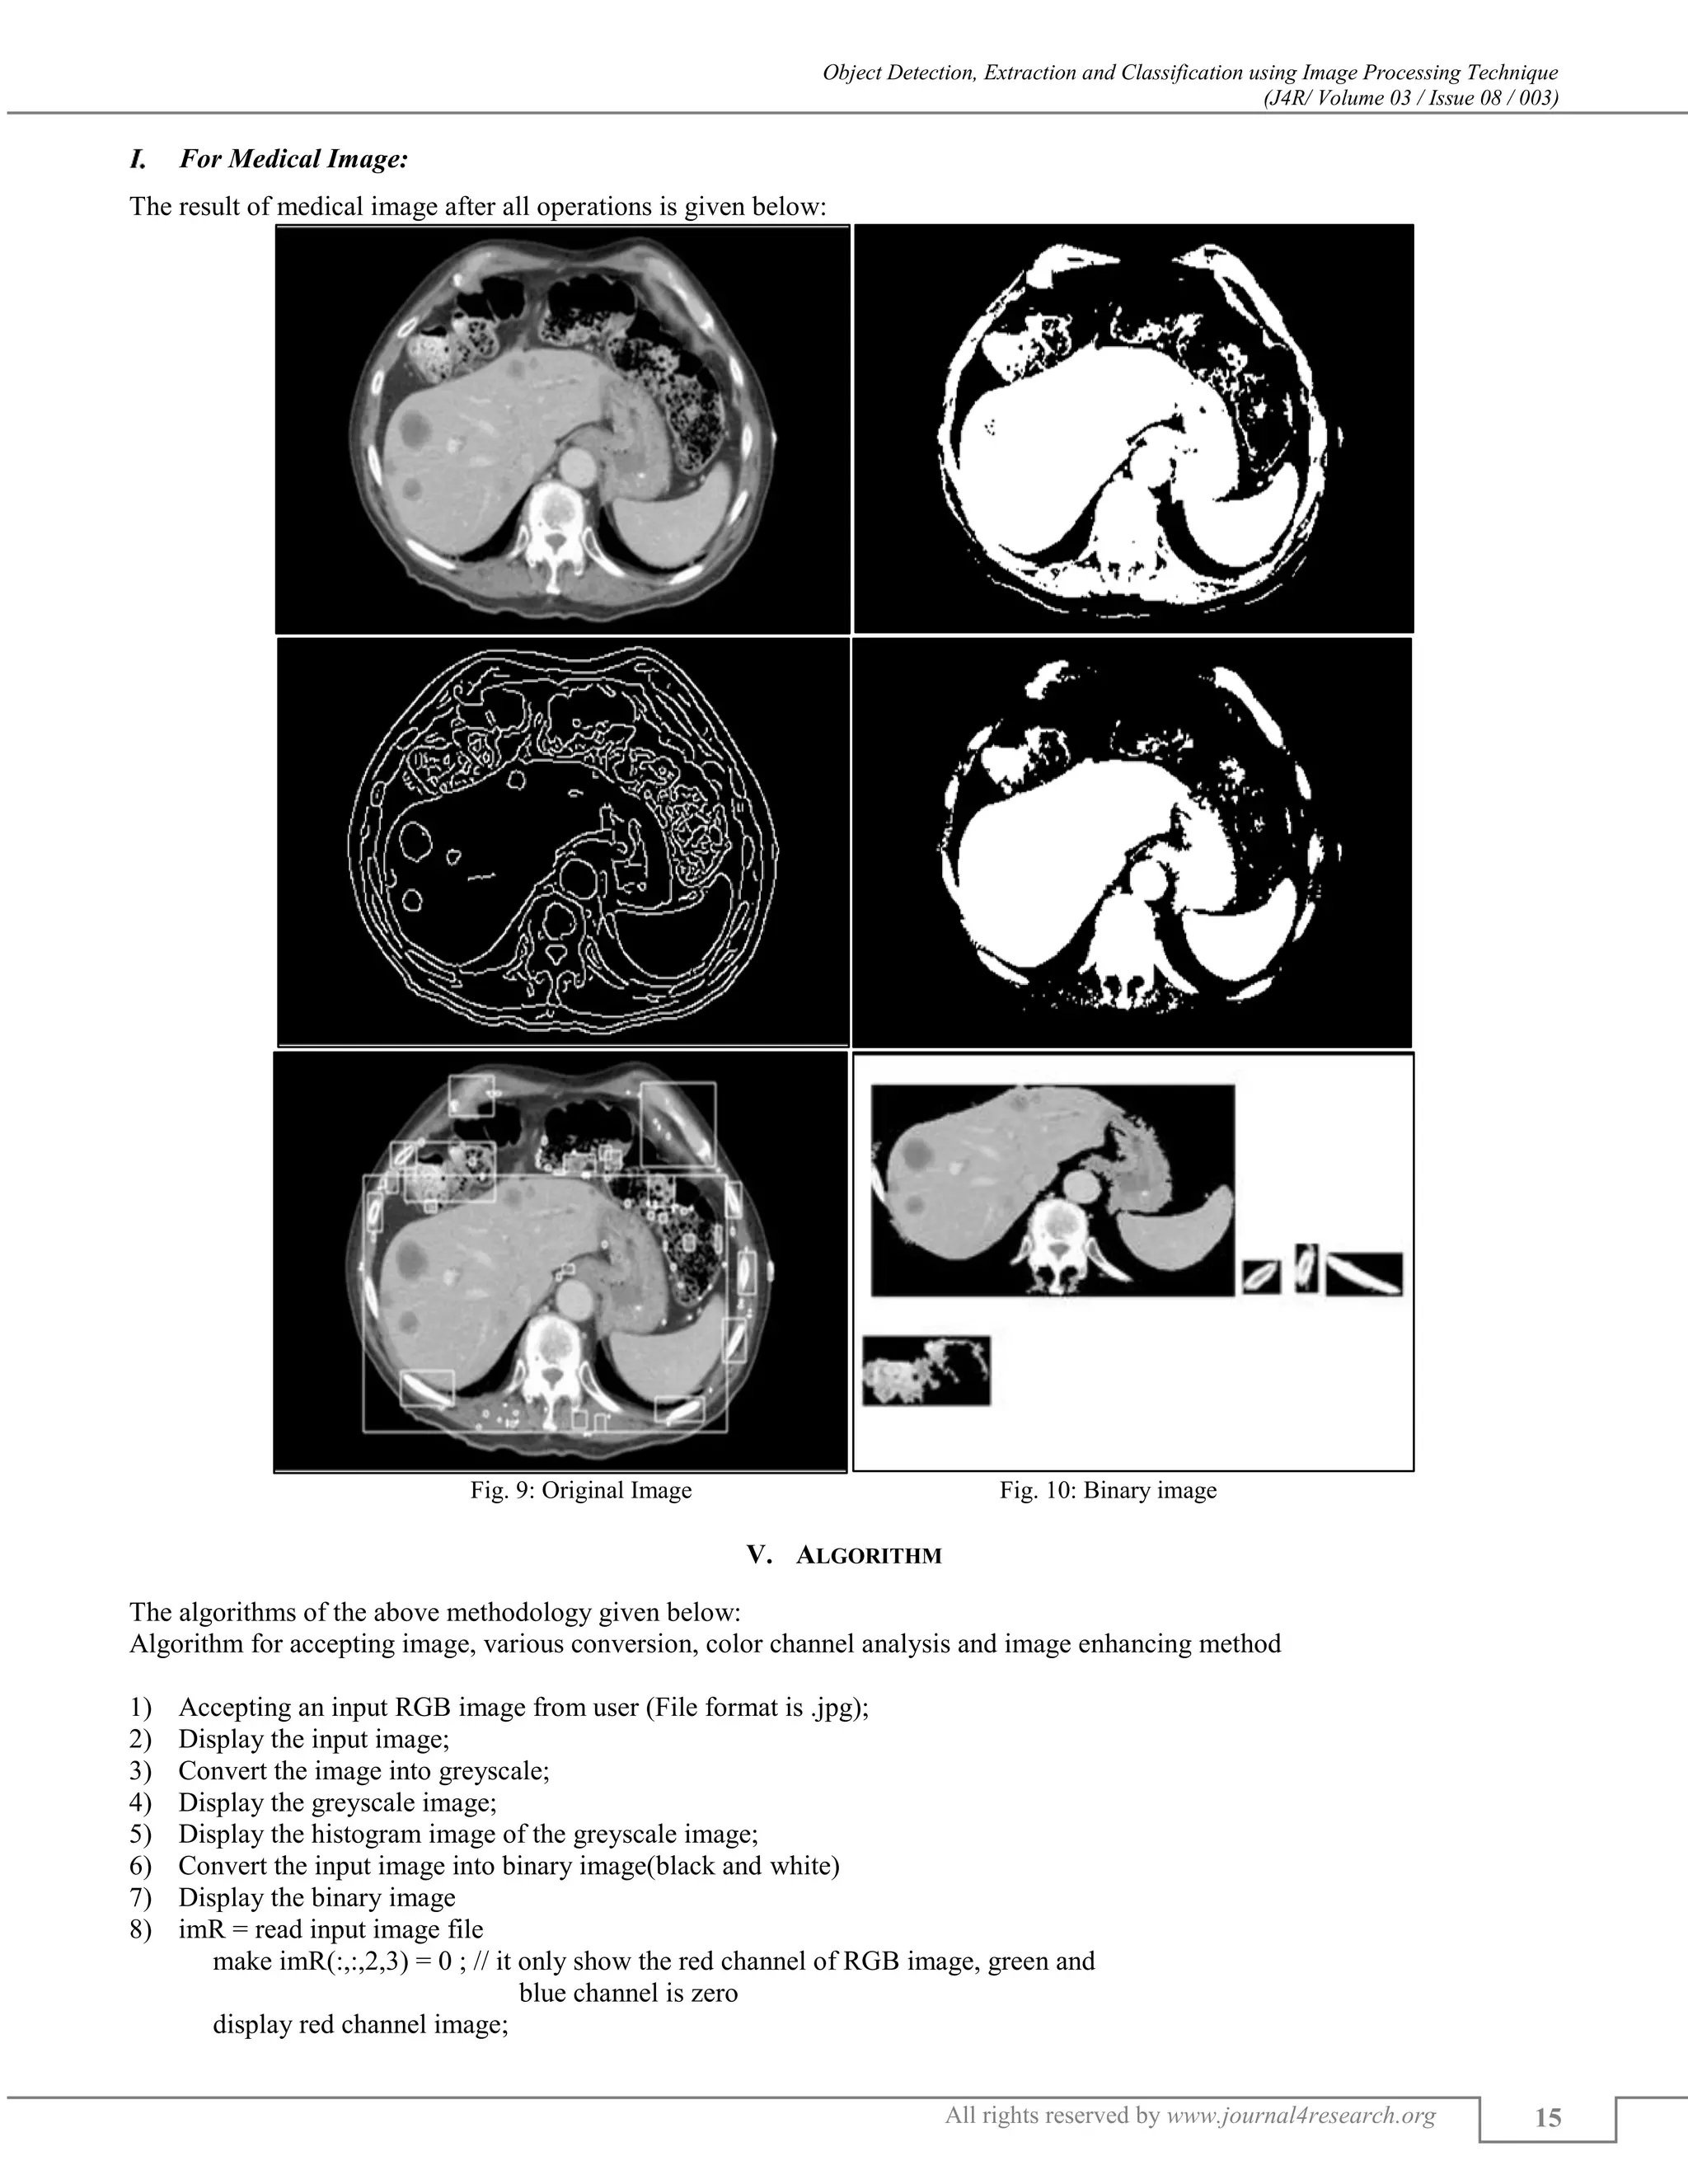

For Medical Image:

Medical images are special images, they are RGB image but it’s not color image. Therefore, for thresholding it has not needed to

The result of medical image after all operations is given below:

Fig. 9: Original Image Fig. 10: Binary image